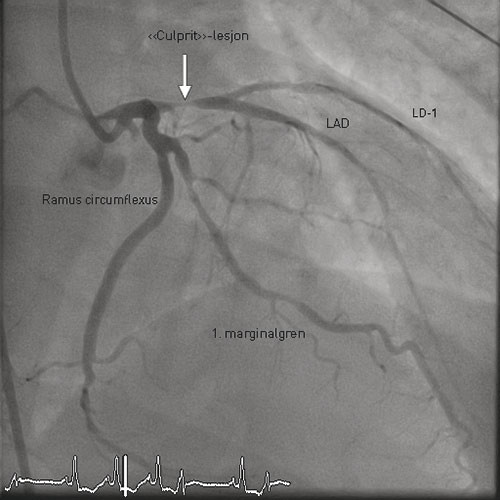

Umiddelbart etter ankomst til universitetssykehuset ble pasienten tatt til angiografilaboratoriet. Koronar angiografi viste trekarssykdom med stenose proksimalt i fremre nedadstigende gren av venstre koronararterie (LAD), stenose på en marginalgren fra ramus circumflexus og flere stenoser i høyre koronararterie (fig 1). LAD-stenosen i ble ansett å ligge bak symptomene (være «culprit»-lesjonen), og det ble der gjort perkutan koronar intervensjon med implantasjon av konvensjonell metallstent – med godt angiografisk resultat.